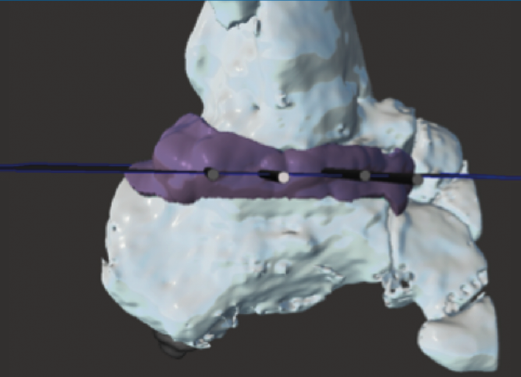

Figura 2. Modelo 3D del defecto del astrágalo.

- Obtención de la forma real del defecto combinando el astrágalo con una imagen especular del astrágalo contralateral (Figura 2).

- Impresión 3D del defecto del astrágalo y guía para la colocación de las agujas (Figura 3).